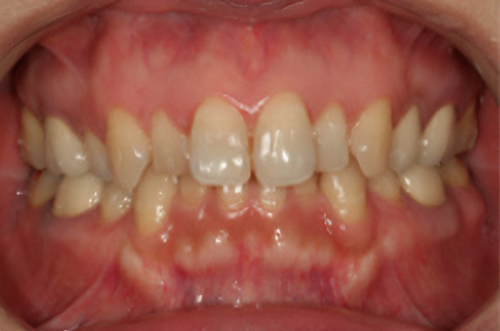

黒ずんだ歯肉の色をお薬で、キレイなピンク色の歯肉にします。

塗り薬の麻酔と薬液だけで10分程度、2回の治療でキレイなピンク色に。-

術前

術後

価格

- > ガムピーリング:上下歯肉2回分 33,000円

※ガムピーリングの効果には個人差があります。

リスク

- > 一時的に沁みることがある。

- > 個人差がある。

- > 色素が深い場合は変化しない部位が残ることがある。

副作用:一時的に歯肉が沁みることがある。1週間程度歯肉は白くなる。